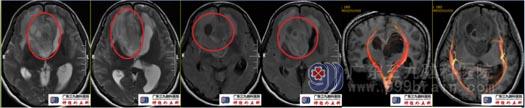

术前头颅MRI示右侧额颞叶、右侧基底节区、透明隔区及左侧额叶示一团块状不均匀长T1、长T2异常信号影,Flair序列呈高信号,间杂囊状明显长T1、长T2异常信号影,范围约62mm×56mm×43mm,增强后病变局部片状、斑片状、环状不均匀异常强化,周围示斑片状Flair序列高信号水肿影,累及胼胝体压部,视交叉、右侧大脑脚、右侧侧脑室前角、第三脑室、双侧侧脑室室间孔不同程度受压。ASL:右侧额颞叶、右侧基底节区、透明隔区及左侧额叶团块状病灶变低-稍高灌注;DTT(白质纤维束三维重建)右侧额颞叶、透明隔区及左侧额叶团块状病灶内纤维紊乱、中断;右侧皮质脊髓束显示稍稀少;双侧枕额束前份、右侧扣带束显示稀少;胼胝体束显示紊乱,请结合临床。影像学诊断:右侧额颞叶、右侧基底节区、透明隔区及左侧额叶占位性病变,考虑偏高级别成人弥漫性胶质瘤。